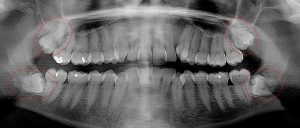

This 19 year old patient has all four 3rd molars present (circled). Only the upper left 3rd molar has fully erupted. The lower left 3rd molar is partially exposed and decaying while the lower right soft tissue impacted, both requiring extraction. Note the double crown on the upper right third molar.